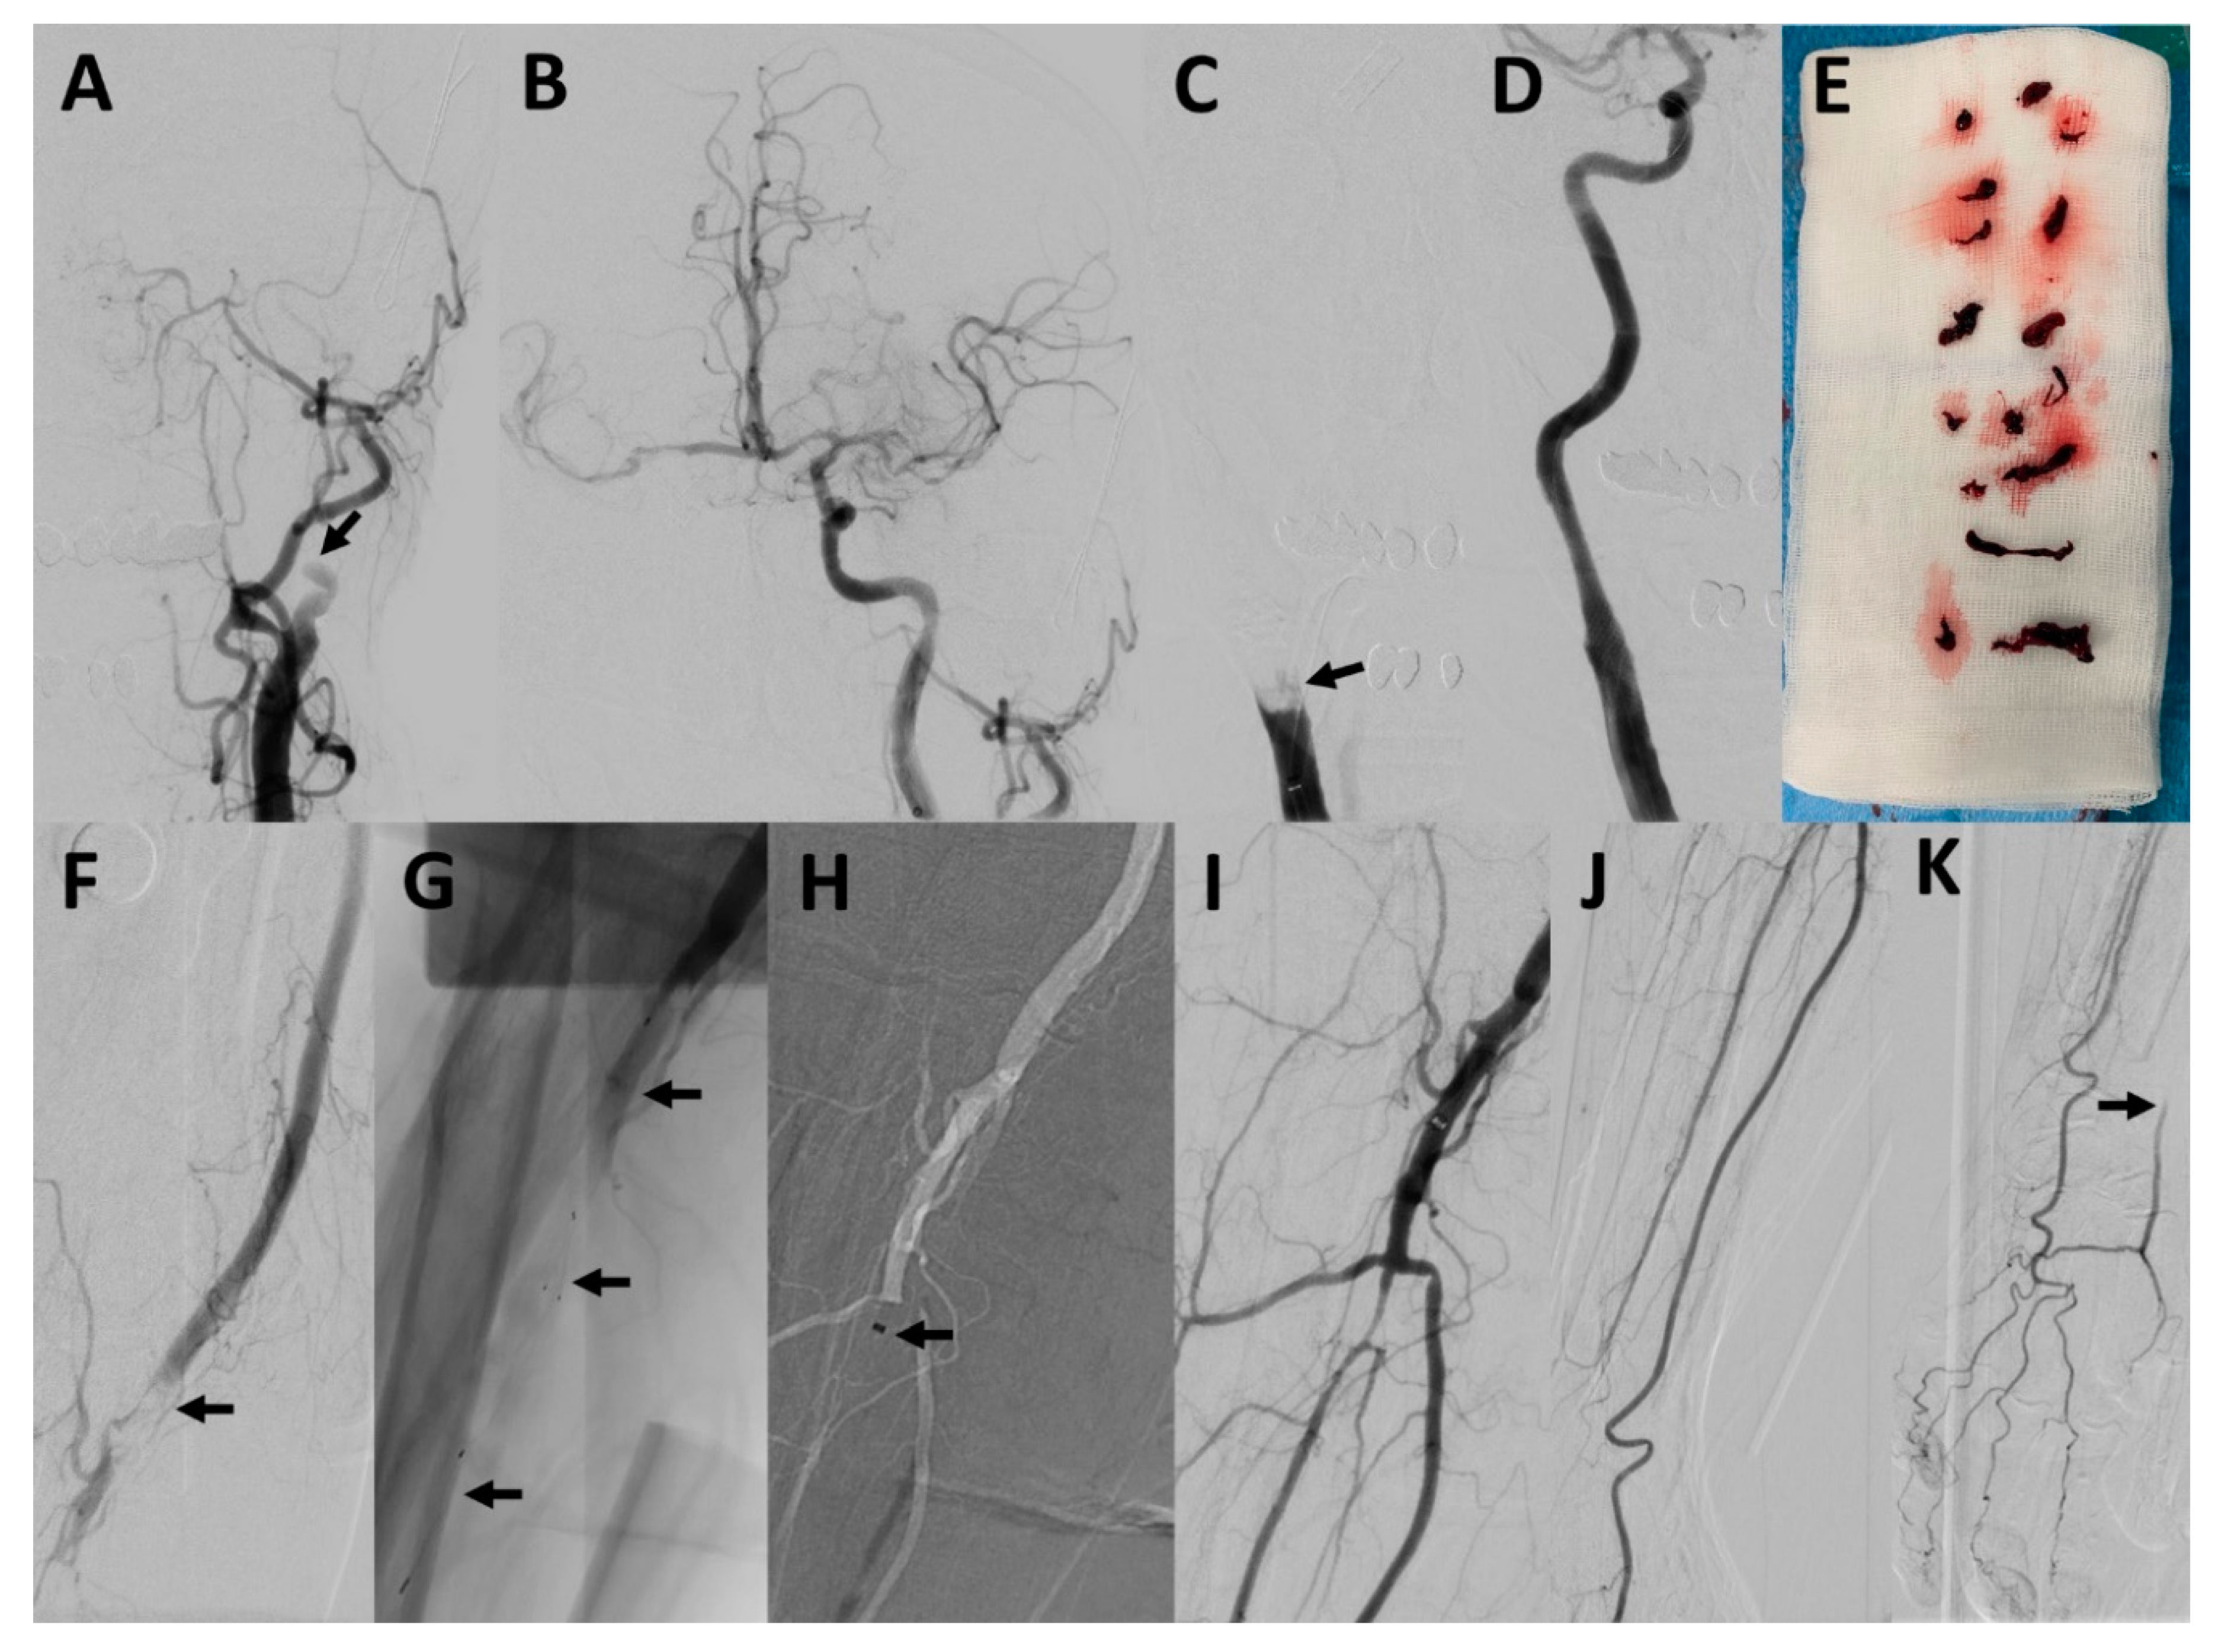

Concomitant Acute Ischemic Stroke and Upper Extremity Arterial Occlusion: Feasibility of Mechanical Thrombectomy of the Upper Limb Using Neurointerventional Devices and Techniques

3. Results